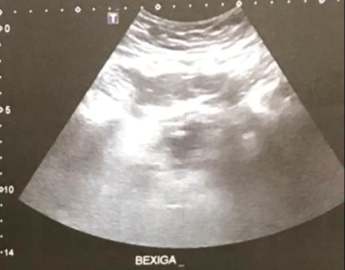

- USG – dilatação bilateral, massa vesical

Recidiva de neoplasia de próstata ??

Neoplasia de Bexiga ??